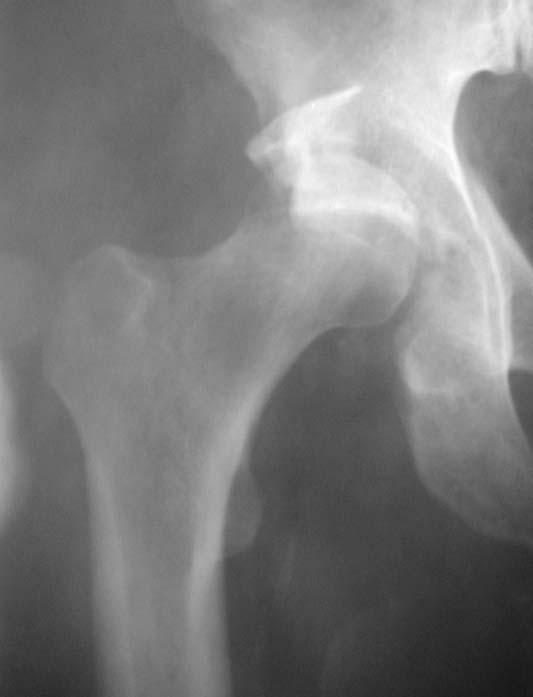

Уважаемые коллеги!Мужчина, 40 лет. Травма несколько месяцев назад. Получил закрытый вывих правого тазобедренного сустава и перелом вертлужной впадины (сним.1).Лечился скелетным вытяжением. Сейчас (сним.2) жалобы на боли, ограничение движений. Вопрос: тактика лечения (эндопротезирование и/или восстановительная операция, иное)?С уважением,А.В.Владзимирский

Вывих, похоже, вообще не был устранен. Или из-за дефекта заднего края сразу рецидивировал.